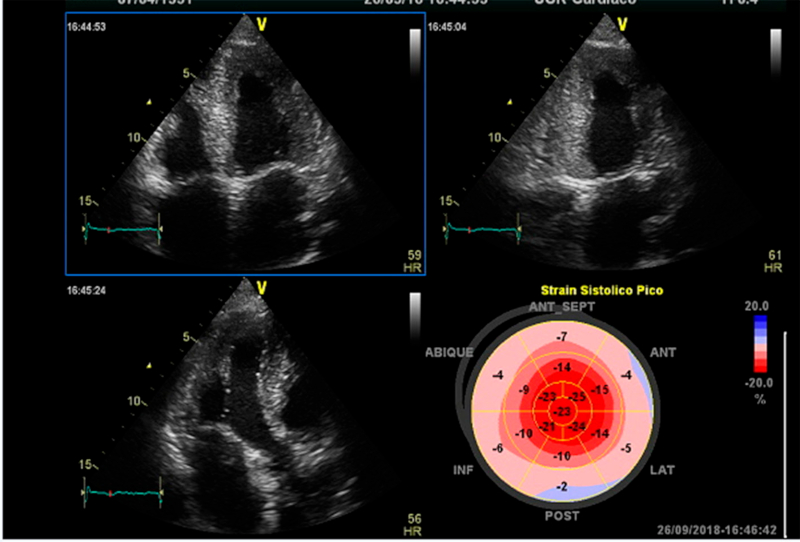

No solo la función de la cámara está afectada, sino también la función de la fibra miocárdica (Figura 1). 16,17,18 La prevalencia de alteración del strain longitudinal bidimensional en la AC oscila entre el 93% y 100%, aún con función sistólica conservada. 19 En cualquiera de las formas de AC, la deformación sistólica (por strain longitudinal) se encuentra conservada en los segmentos apicales y significativamente reducida en valores absolutos en los segmentos medios y basales. Este patrón de preservación apical mejora la especificidad en el diagnóstico. 10,20 Una relación del strain apical/ strain basal + strain medial >1 permitió diferenciarla de la miocardiopatía hipertrófica (sensibilidad del 93%, especificidad del 82% y área bajo la curva de 0,91) y de la estenosis aórtica (sensibilidad del 93%, especificidad del 82% y área bajo la curva de 0,97). 22 Este hallazgo fue confirmado también en la enfermedad de Fabry y la ataxia de Friedrich (Figura 1). En este sentido, un punto de corte >4,1 en la relación entre la FEVI y el strain longitudinal sistólico presentó mejor performance en el diagnóstico diferencial con otras formas de hipertrofia (sensibilidad 90%, especificidad 92% y área bajo la curva de 0,9). 23 Además, en pacientes AL, el strain ventricular promedio longitudinal es un potente predictor de la evolución clínica, superior a los elementos predictores del ecocardiograma Doppler 21.